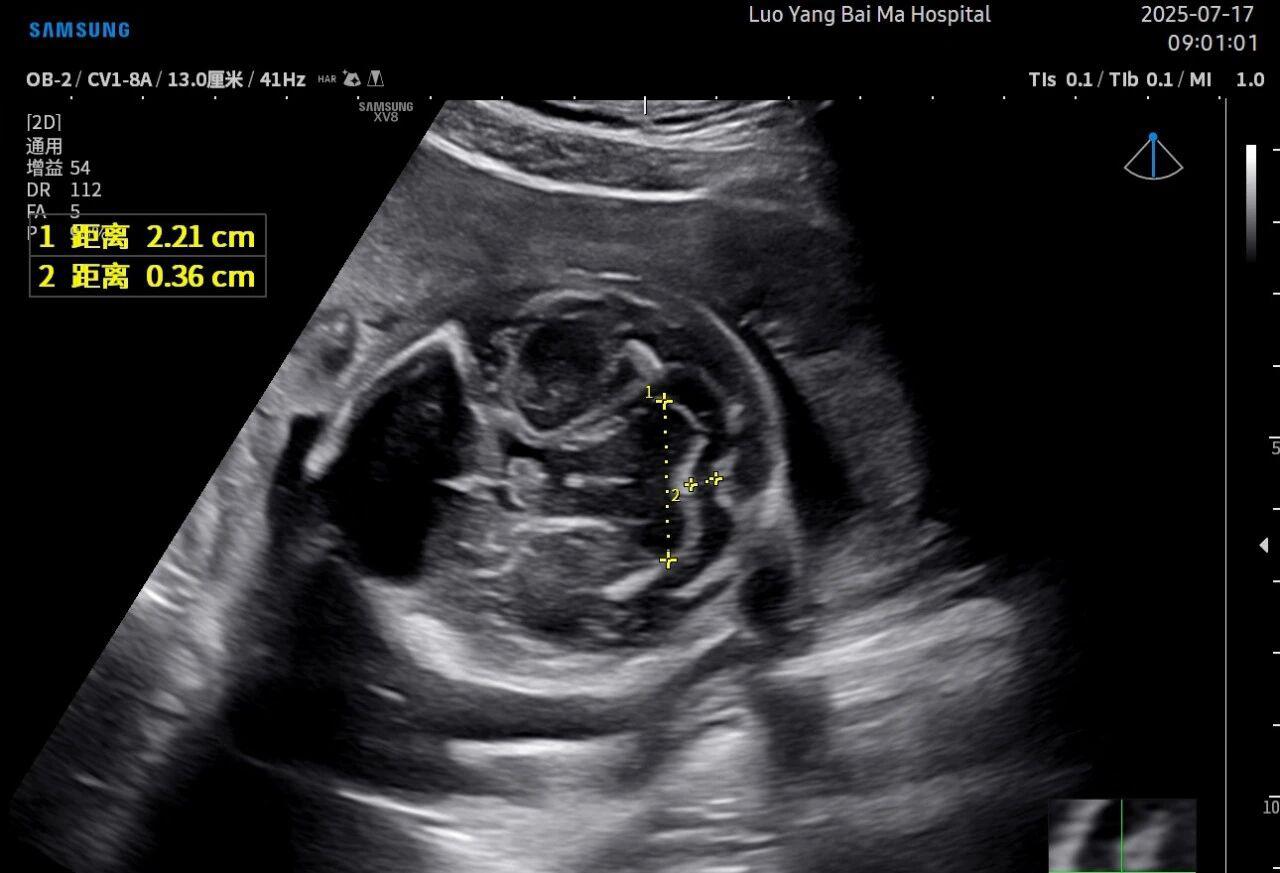

3. AI智能辅助,提升诊断效率与客观性

这是5D技术的核心优势之一。系统内置了强大的智能化大数据分析功能和AI辅助诊断工具。例如,在进行胎儿颈项透明层(NT)测量、胎儿长骨(LB)测量等关键生物学指标评估时,5D智能系统可以自动识别解剖层面、智能勾勒测量范围并进行计算。这不仅大大缩短了检查时间,更重要的是,它通过标准化的智能算法减少了因人为操作可能产生的误差,使诊断结果更加客观、可靠。